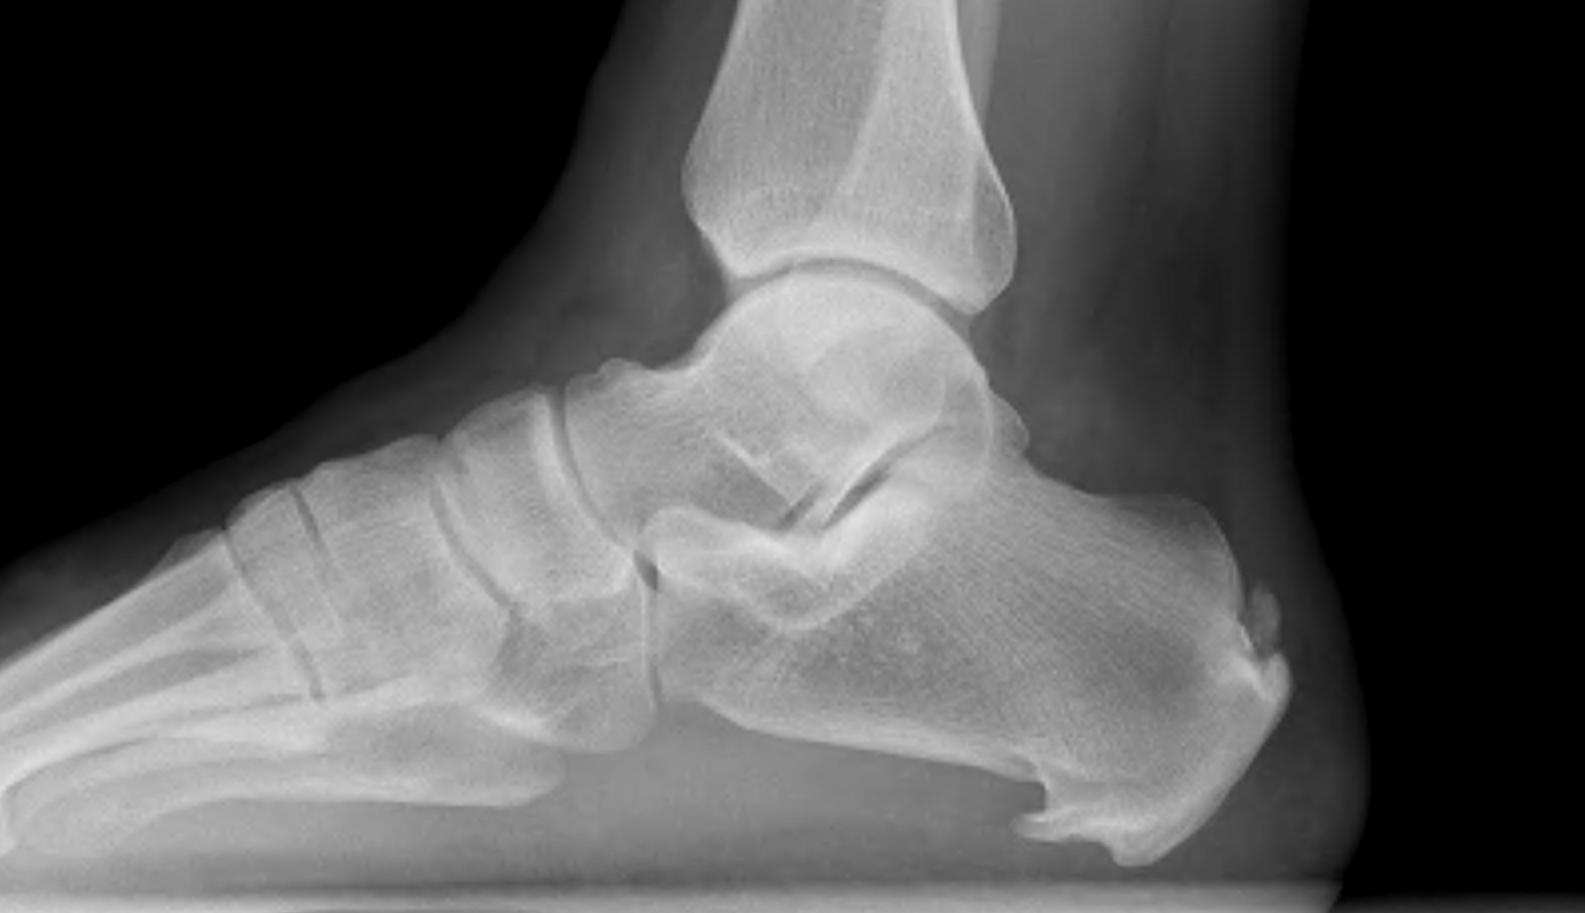

X-ray

Calcaneal spurs

Moroney et al Foot Ankle Spec 2014

- 1100 foot xrays

- calcaneal spurs in 12%

- more common women / older / diabetes / OA

- associated with foot pain

Zhou et al J Foot Ankle Surg 2015

- 2 types calcaneal spur

- Type A: superior to plantar fascia

- Type B: located within plantar fascia

Calcaneal spur above plantar fascia which is thickened with tears